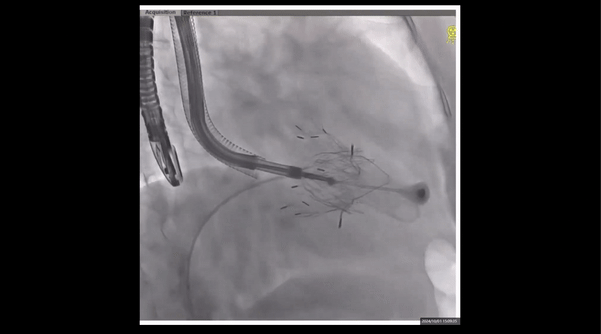

術(shù)前右室造影

夾持件位置確認(rèn)

室間隔位置確認(rèn)